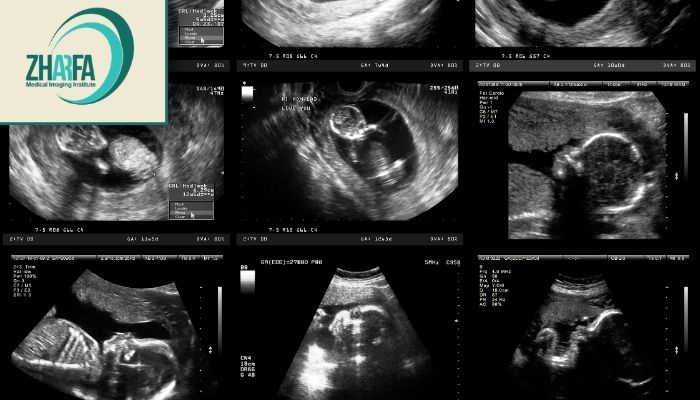

اهمیت سونوگرافی در دوران بارداری

یکی از بهترین ابزارها برای اطمینان از روند طبیعی رشد جنین تصویربرداری پزشکی است. این روش نهتنها به پزشک کمک میکند تا شرایط مادر و جنین را بهتر بررسی کند بلکه آرامش خاطر بیشتری نیز به خانواده میدهد.

انواع سونوگرافی دوران بارداری

ترانسواژینال: در اوایل بارداری برای بررسی رحم و جنین.

دوبعدی (2D): برای مشاهده رشد و ضربان قلب جنین.

سهبعدی (3D): امکان مشاهده واضحتر چهره و اندام جنین.

چهاربعدی (4D): نمایش حرکات زنده جنین در لحظه.

داپلر: بررسی جریان خون در بند ناف و عروق جنین.